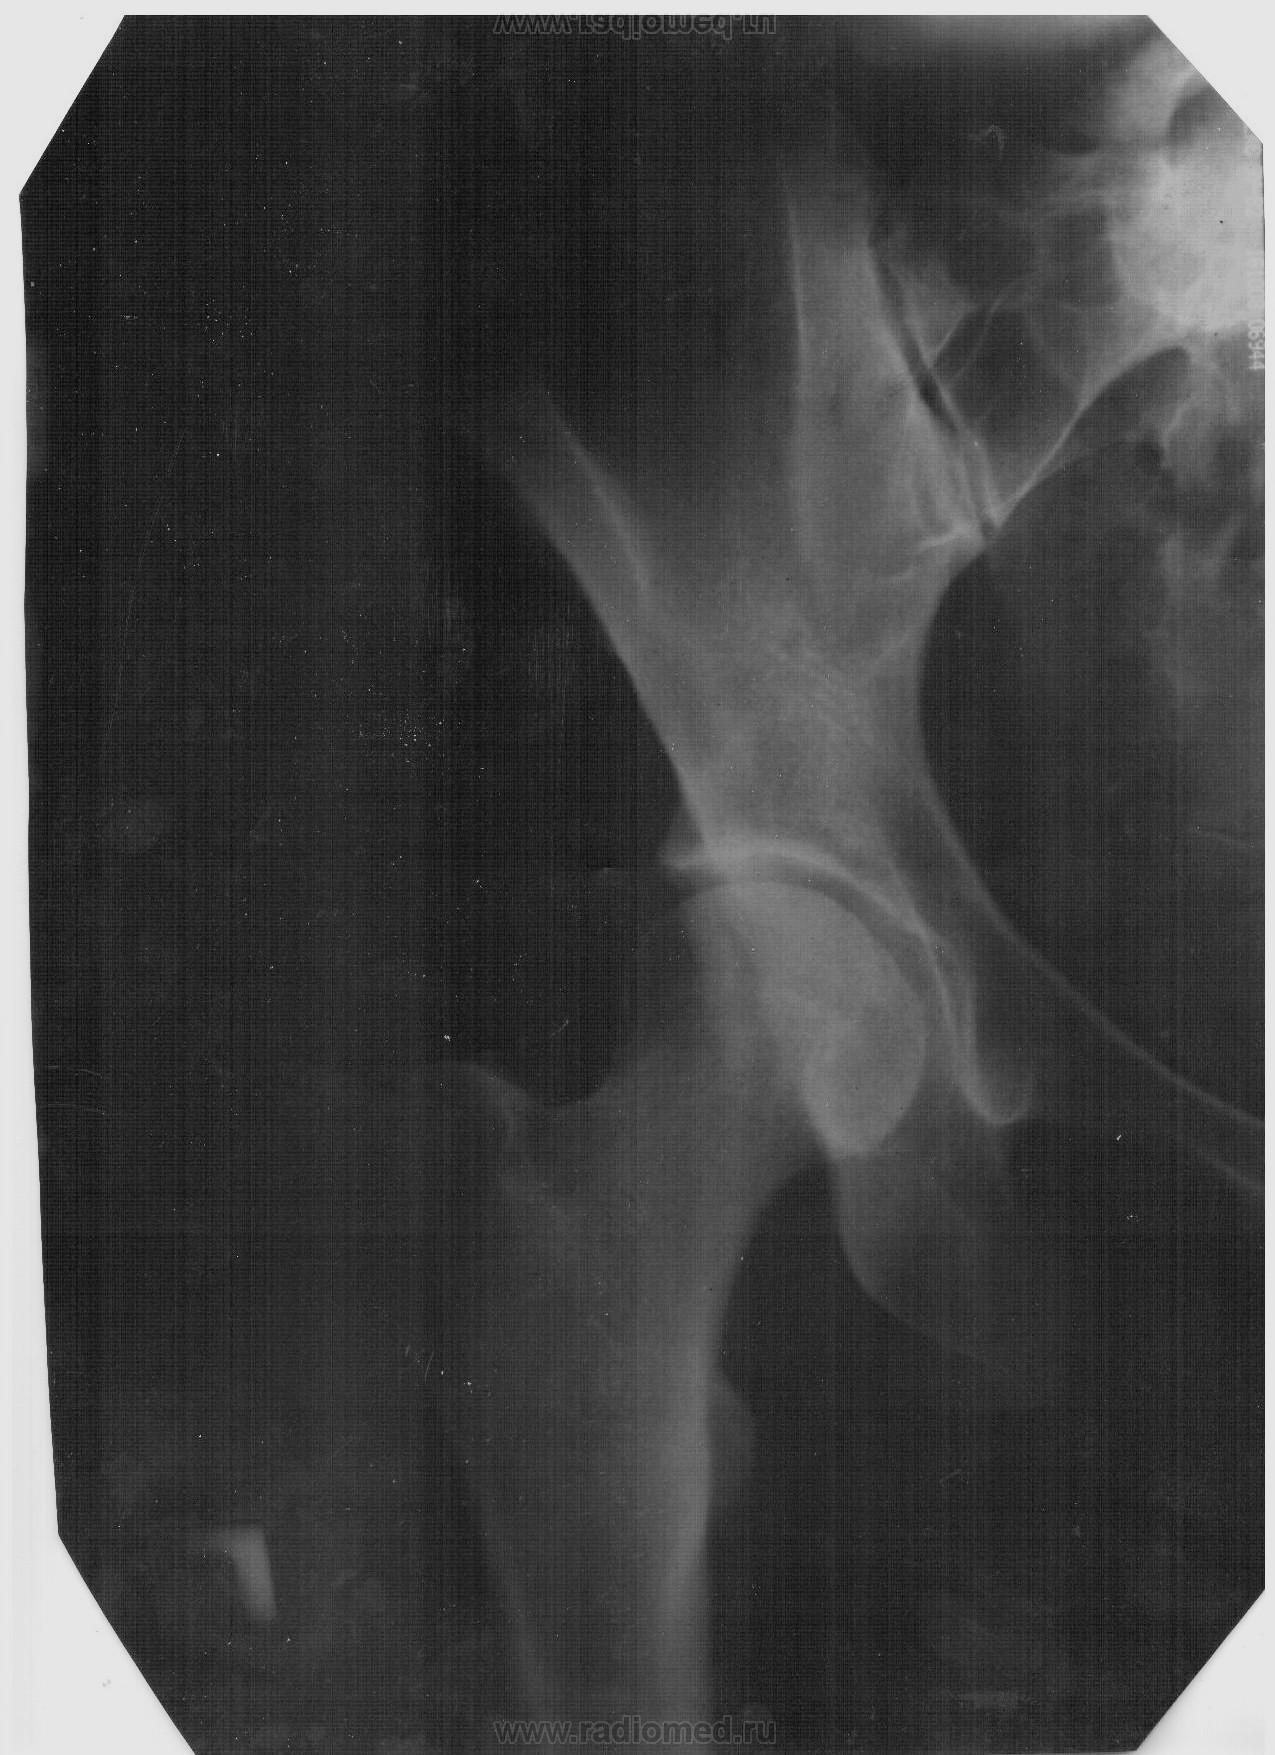

неполный разрыв лонного сочленения или разрыв связочно-капсульного аппарата правого тазобедренного сустава?

Здравствуйте! Уважаемые эксперты-рентгенологи!!! после дтп мне на основании этих снимков были поставлены вот такие диагнозы.Сразу после дтп Разрыв связочно-капсульного аппарата правого тазобедренного сустава,прошло 4 месяца назначили судебно-медицинскую экспертизу где ни какой из диагнозов не подтверждается (постарался адвокат второй стороны) теперь хочу добиться назначения повторной экспертизы.Очень хотелось бы узнать Ваше авторитетное мнение.Заранее благодарна

Уважаемая Лариса, Ваши снимки перефотографированы Вами не совсем удачно, качество изображения не дает возможности высказать мнение. Лонное сочленение на одном из снимков в крае плёнки, судить о разрыве симфиза проблематично.

Качество рентгенограмм очень низкое. Поэтому могу предположить, что имеется перелом задней стенки вертлужной впадины с незначительным смещением отломка.

В проекции головки бедра подозрение на трещину.

Разрыв связочно-капсульного аппарата правого тазобедренного сустава -  диагноз клинический, на рентгенограммах не виден.

Если уж переделывать, то не снимок, а МСКТ. Переломы на них видны и лучше и дольше.

снимочек подредактировать, можно заподозрить трещину головки бедра. Симфиз - вроде  без патологии.